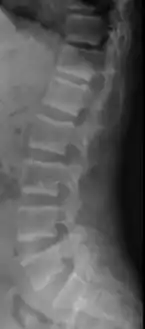

X-ray of a subtle "rugger jersey spine" due to sclerotic bands adjacent to the vertebral endplates.[17]

CT scan of the same case.[17]